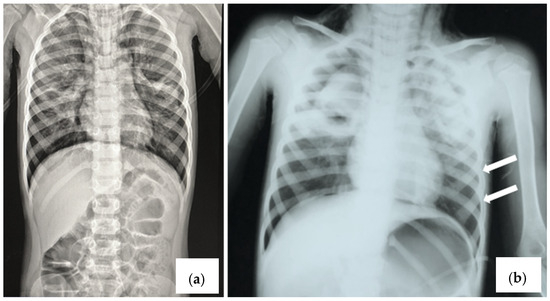

2.4. Case 4

3. Discussion